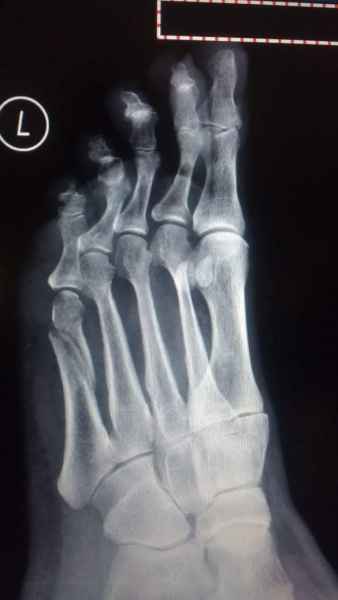

La marcha no solo es característica de la especie humana sino también de cada persona, y más aún varía según el estado de ánimo del momento. Una patología en los pies, se traduce en el rostro, en el ánimo, en el psiquismo. No sólo el dolor produce estos efectos, también un pie deformado o poco estético. En nuestra sociedad, la estética constituye un valor muy apreciado y estas alteraciones causan vergüenza fundamentalmente en las mujeres, que esconden en la playa sus pies en la arena y no pueden usar calzados elegantes.

Tanto la estructura del pie como su funcionalismo que es la marcha, pueden ser asiento y manifestación respectivamente de alteraciones locales ó sistémicas, por lo que su cuidadoso examen resulta de extrema utilidad diagnóstica.